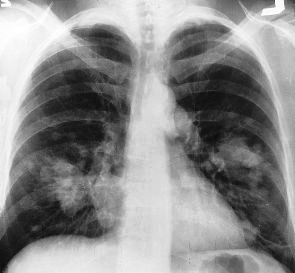

Il rapporto infermiere-paziente: storie di tutti i giorniNon dimenticherò mai A., un paziente sulla quarantina che si presentò nell’unità di assessment per dolore in quadrante superiore destro. Sospettando una litiasi della colecisti, decisi di effettuare esami ematici e prenotare un’ecografia urgente. Come da protocollo, però, prenotai una lastra del torace per escludere una possibile perforazione (interpretabile come aria sotto il diaframma). La lastra si presentò pressappoco come quella qui accanto. Allarmato da un’immagine che mostrava delle “ombre sospette”, chiamai urgentemente il chirurgo di turno, chiedendo di controllare l’RX. Dall’altro capo del telefono mi rispose: “Quelle sembrano metastasi, facciamogli una TAC”. La prenotai e il risultato fu quello sospettato. Le lesioni tumorali nei polmoni erano secondarie a metastatizzazione di lesione carcinomatosa del colon.